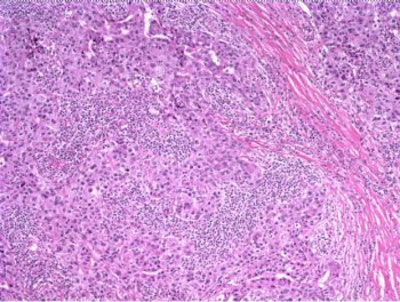

The patient underwent a lumpectomy with sentinel node biopsy. The pathology again showed extensive mitoses consistent with grade III invasive ductal carcinoma. Figure 4 (below) shows a representative microscopic section of the mass 4 cm from the nipple at a magnification factor of 100x. Figure 5 is the same area magnified 400x. Figure 6 shows a representative microscopic section from the other mass, which was 3 cm from the nipple magnified 100x. Figure 7 is magnified 400x. The tumors were estrogen receptor- and progesterone receptor-negative. Two sentinel nodes were negative.

Figure 4: Above, IDC right breast, 10 o'clock, 4 cm from the nipple magnified 100x. Figure 5: Below, IDC right breast, 10 o'clock, 4 cm from the nipple magnified 400x. |